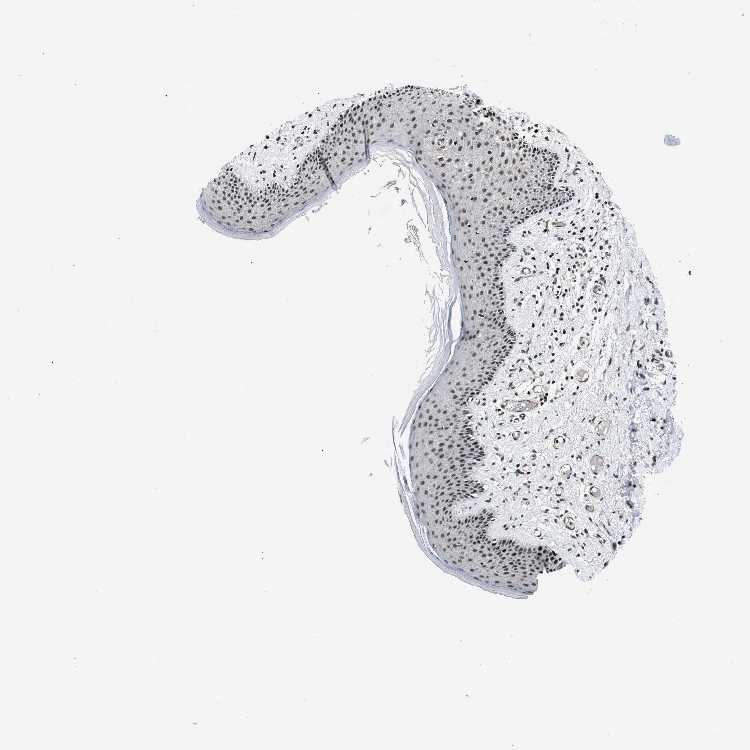

SKIN 2 - Antibody stainingi

Antibody staining in the annotated cell types in the current human tissue is reported as not detected, low, medium, or high, based on conventional immunohistochemistry profiling in selected tissues. This score is based on the combination of the staining intensity and fraction of stained cells.

Each image is clickable and will lead to virtual microscopy that enables deeper exploration of all samples and also displays staining intensity scores, fraction scores and subcellular localization as well as patient and tissue information for each sample.

Antibody HPA018248Antibody HPA019127Antibody CAB009196

Cells in basal layer Medium--

Cells in corneal layer Not detected--

Cells in granular layer Medium--

Cells in spinous layer Medium--

Endothelial cells Medium--

Epidermal cells -HighMedium

Extracellular matrix Not detected--

Fibrohistiocytic cells Medium--

Langerhans cells Medium--

Lymphocytes High--

Melanocytes High--

Vascular mural cells Not detected--